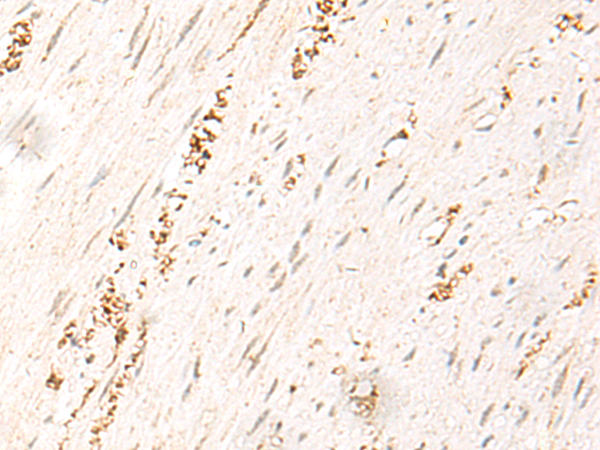

The image is immunohistochemistry of paraffin-embedded Human cervical cancer tissue using P02869(MDFI Antibody) at dilution 1/50. (Original magnification: ×200) |

The image is immunohistochemistry of paraffin-embedded Human colorectal cancer tissue using P02869(MDFI Antibody) at dilution 1/50. (Original magnification: ×200) |